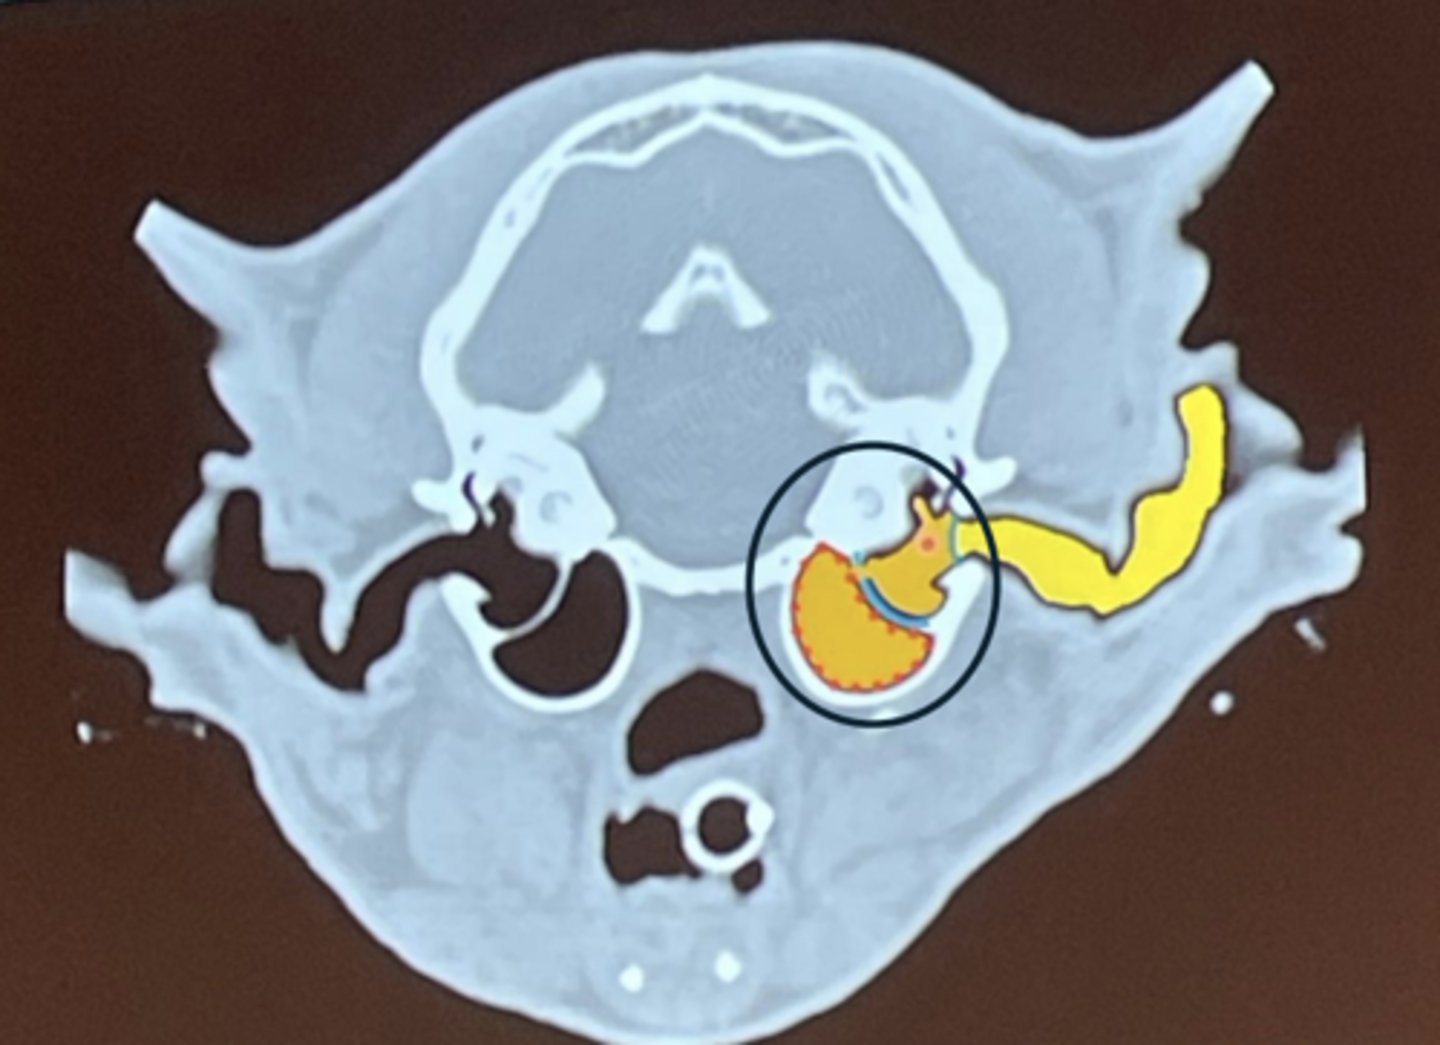

What is being highlighted in yellow?

external ear

What is circled?

middle ear